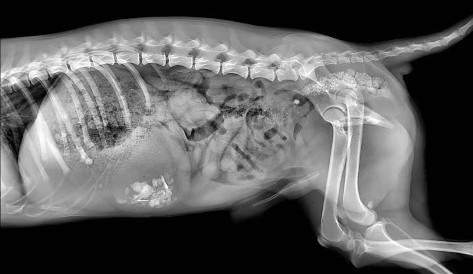

宠物DR作为一种数字化X射线检查设备,可以针对宠物的头部、腹部、髋关节等不同部位进行X射线成像,辅助宠物医生进行及时精确的诊疗,通过调查数据显示,2020-2021年宠物DR市场需求强劲,由于其辅助诊断功能强大,已成为宠物医院是必购医疗器械。